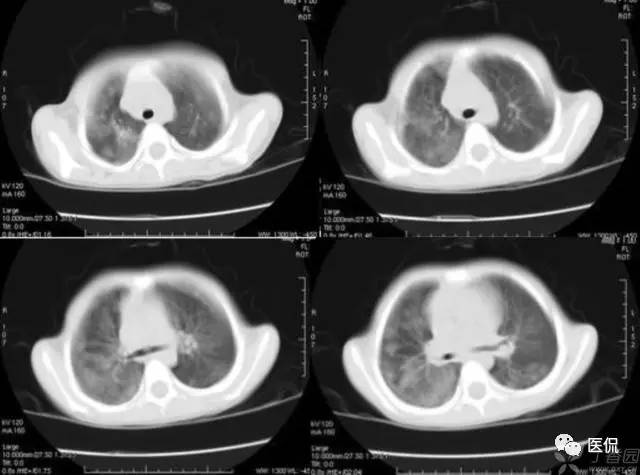

磨玻璃密度(GGO)

胸部影像上表现为肺密度的轻度增加,透过这种磨玻璃影像可以看到肺纹理的影像。该征象包括下属几种情形:1)弥漫型 如严重的急性肺移植排斥反应、早期成人呼吸窘迫综合症、肺水肿、过敏性肺炎、肺出血、各种原因的感染如非典型性肺炎等;2)斑片型 如各种类型的肺炎、肺泡蛋白沉积征、类脂质肺炎、卡氏肺囊虫病以及成人呼吸窘迫综合症等;3)局灶型 肿瘤如肺炎型肺泡癌、肺外伤、肺梗死等,这种类型常常和上述两种的病因相重叠;4)晕型 常见于早期浸袭性肺曲霉菌病,也可见于肺穿刺之后;5)支气管血管型和小叶中心型 如嗜酸性肺炎、结节病、外源性过敏性肺炎、呼吸系支气管炎等,其间前二者多见于支气管血管型,后二者多见于小叶中心型。

磨玻璃影的分布对于鉴别诊断也有帮助:1)呈小叶中心分布时,一般多是早期病变,常为支气管播散,可能是过敏性肺炎或脱屑性间质性肺炎所致;2)呈全小叶分布时,病变边缘清楚;呈部分小叶受累时,病变边缘模糊。前者可见于肺泡蛋白沉积征、药物中毒性肺炎、类脂质肺炎、肺结节病、卡氏肺囊虫病、肺炎吸收期间以及肺出血等;3)呈小叶周围性分布时,多为早期特发性肺纤维化的表现。

1)肺腺癌:

2)含铁血黄素沉着症:

3)特发性肺间质纤维化: